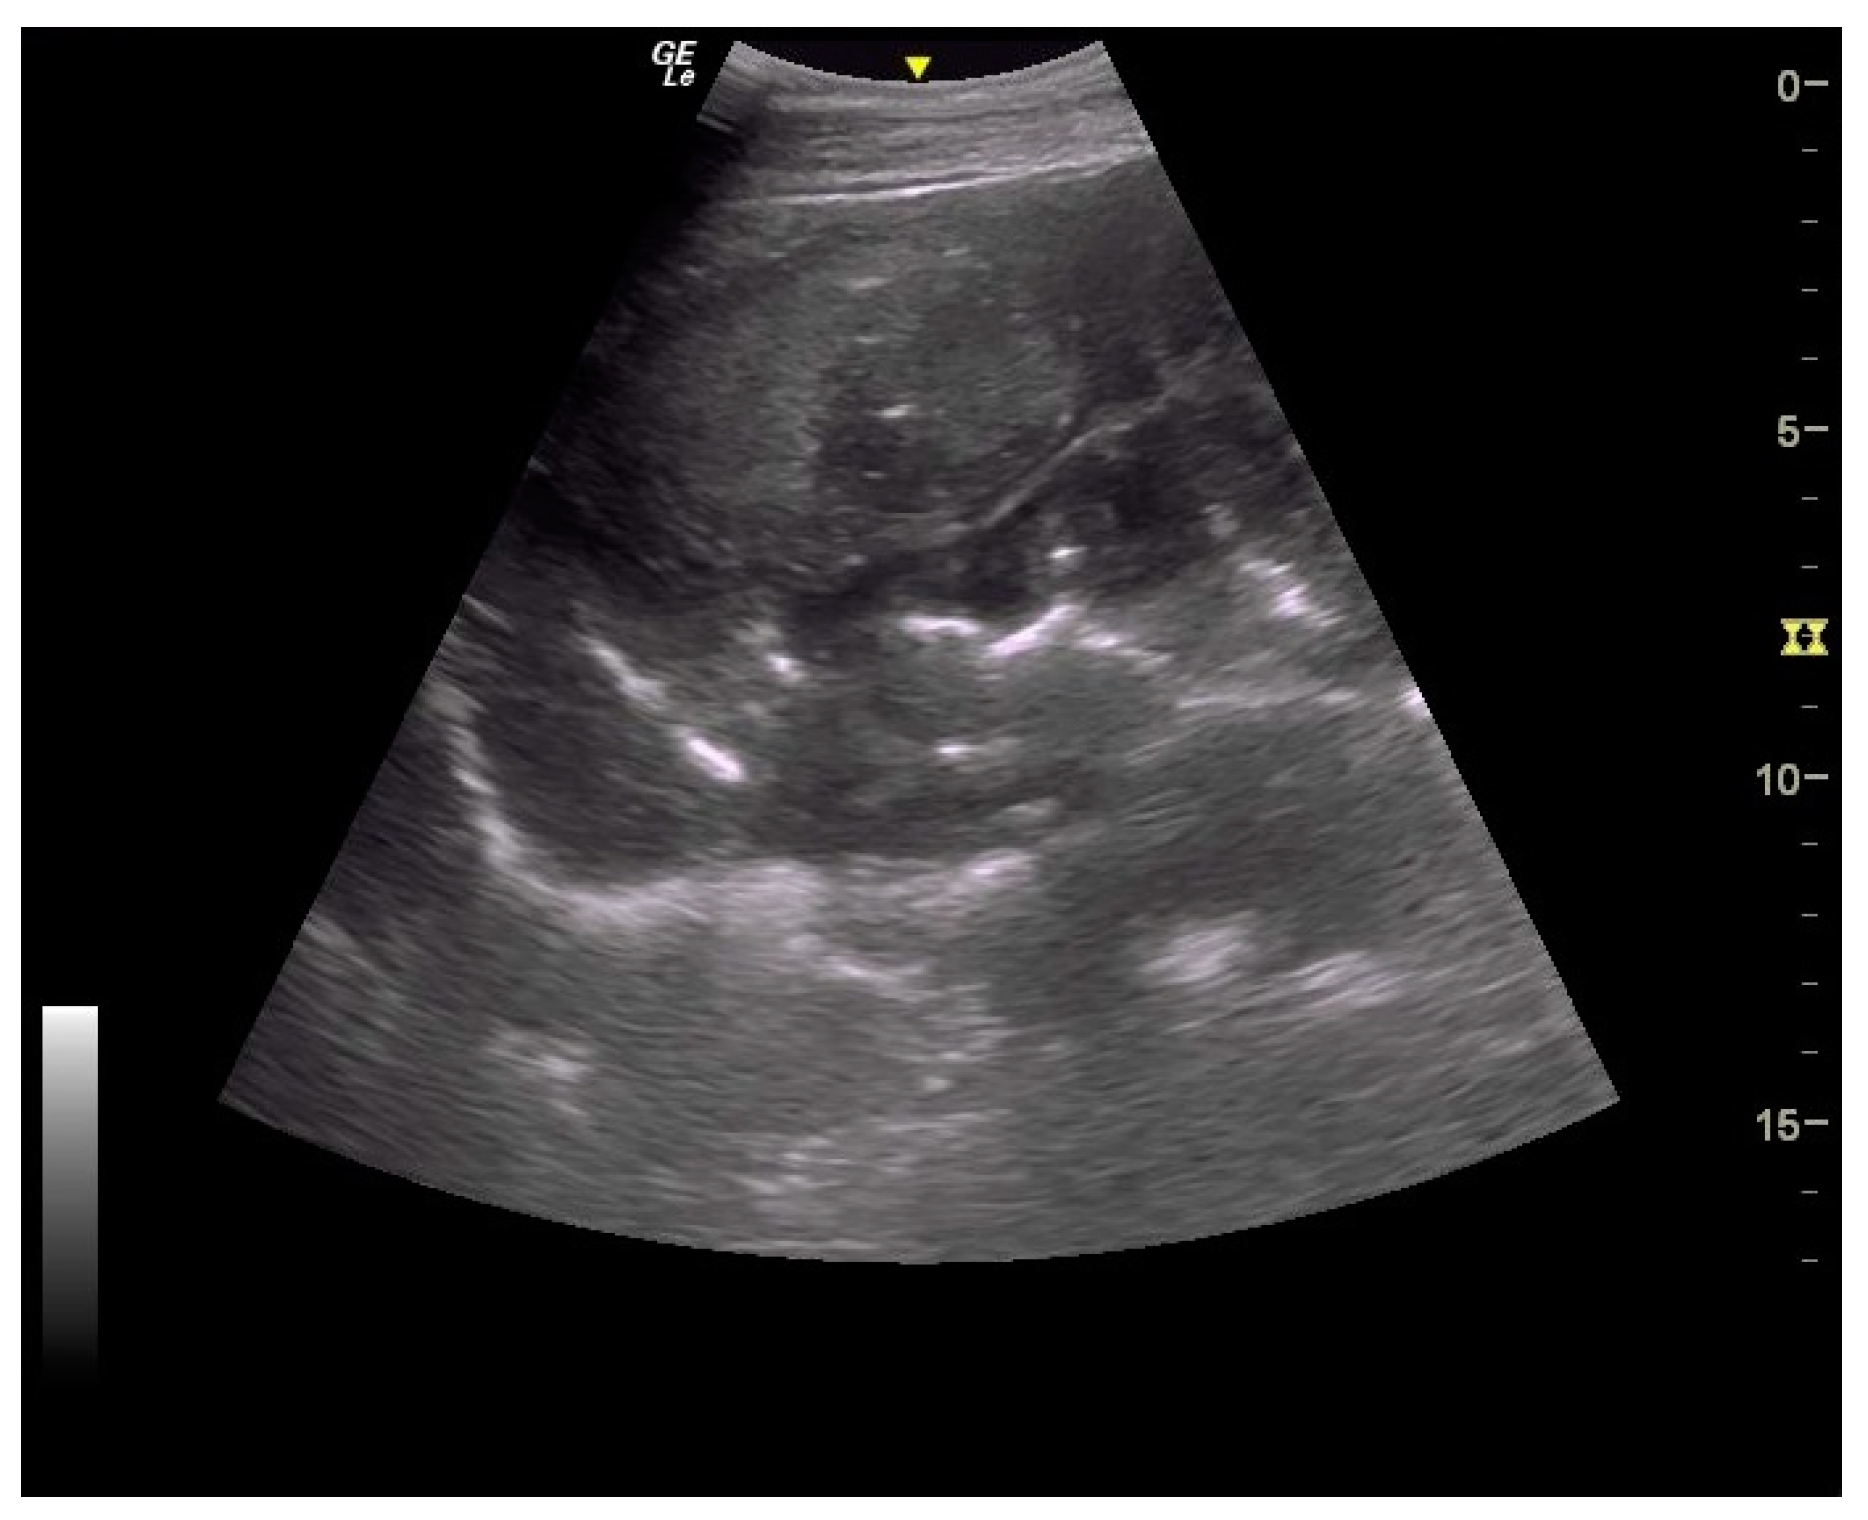

Figure 7.

Ultrasound images of large colon. Very severe thickening of large colon.

Thickening of the colon wall was significantly greater (p = 0.02) among the horses which did not survive (36 ± 19 mm versus 19 ± 6 mm) (Figure 5). Beyond 22 mm of thickness, the horses presenting such damages of the colon had significantly (p = 0.01) lower chances of survive with a positive predictive value of non-survival of 89% (Table 1). Thickening of the small intestine was observed for 35% (6/17) of the horses on which ultrasonography was performed. Abdominal ultrasonography showed severe thickening of the colon wall with values rarely encountered in other diseases with an average of 29 ± 17 mm (Figure 6 and Figure 7).

In addition to the marked seasonality, the clinical presentation was quite typical with an acute to fulminant severe edematous colitis leading to toxic shock, which was complicated in several cases with marked azotemia, increase hepatic or muscle enzymes, and intravascular hemolysis. Although not fully detailed in other studies, the hemato-biochemical results were similar to previous reports [,] and can be easily understood in view of the acute colitis shock. Abdominal ultrasonography examination revealed marked thickening of the large colon wall, especially in non-survivors with values rarely encountered in other diseases. The thickness was so severe that clear measurement was sometimes difficult (Figure 7). This reflects the severe colon edema as it could be observed post-mortem (Figure 11 and Figure 12).